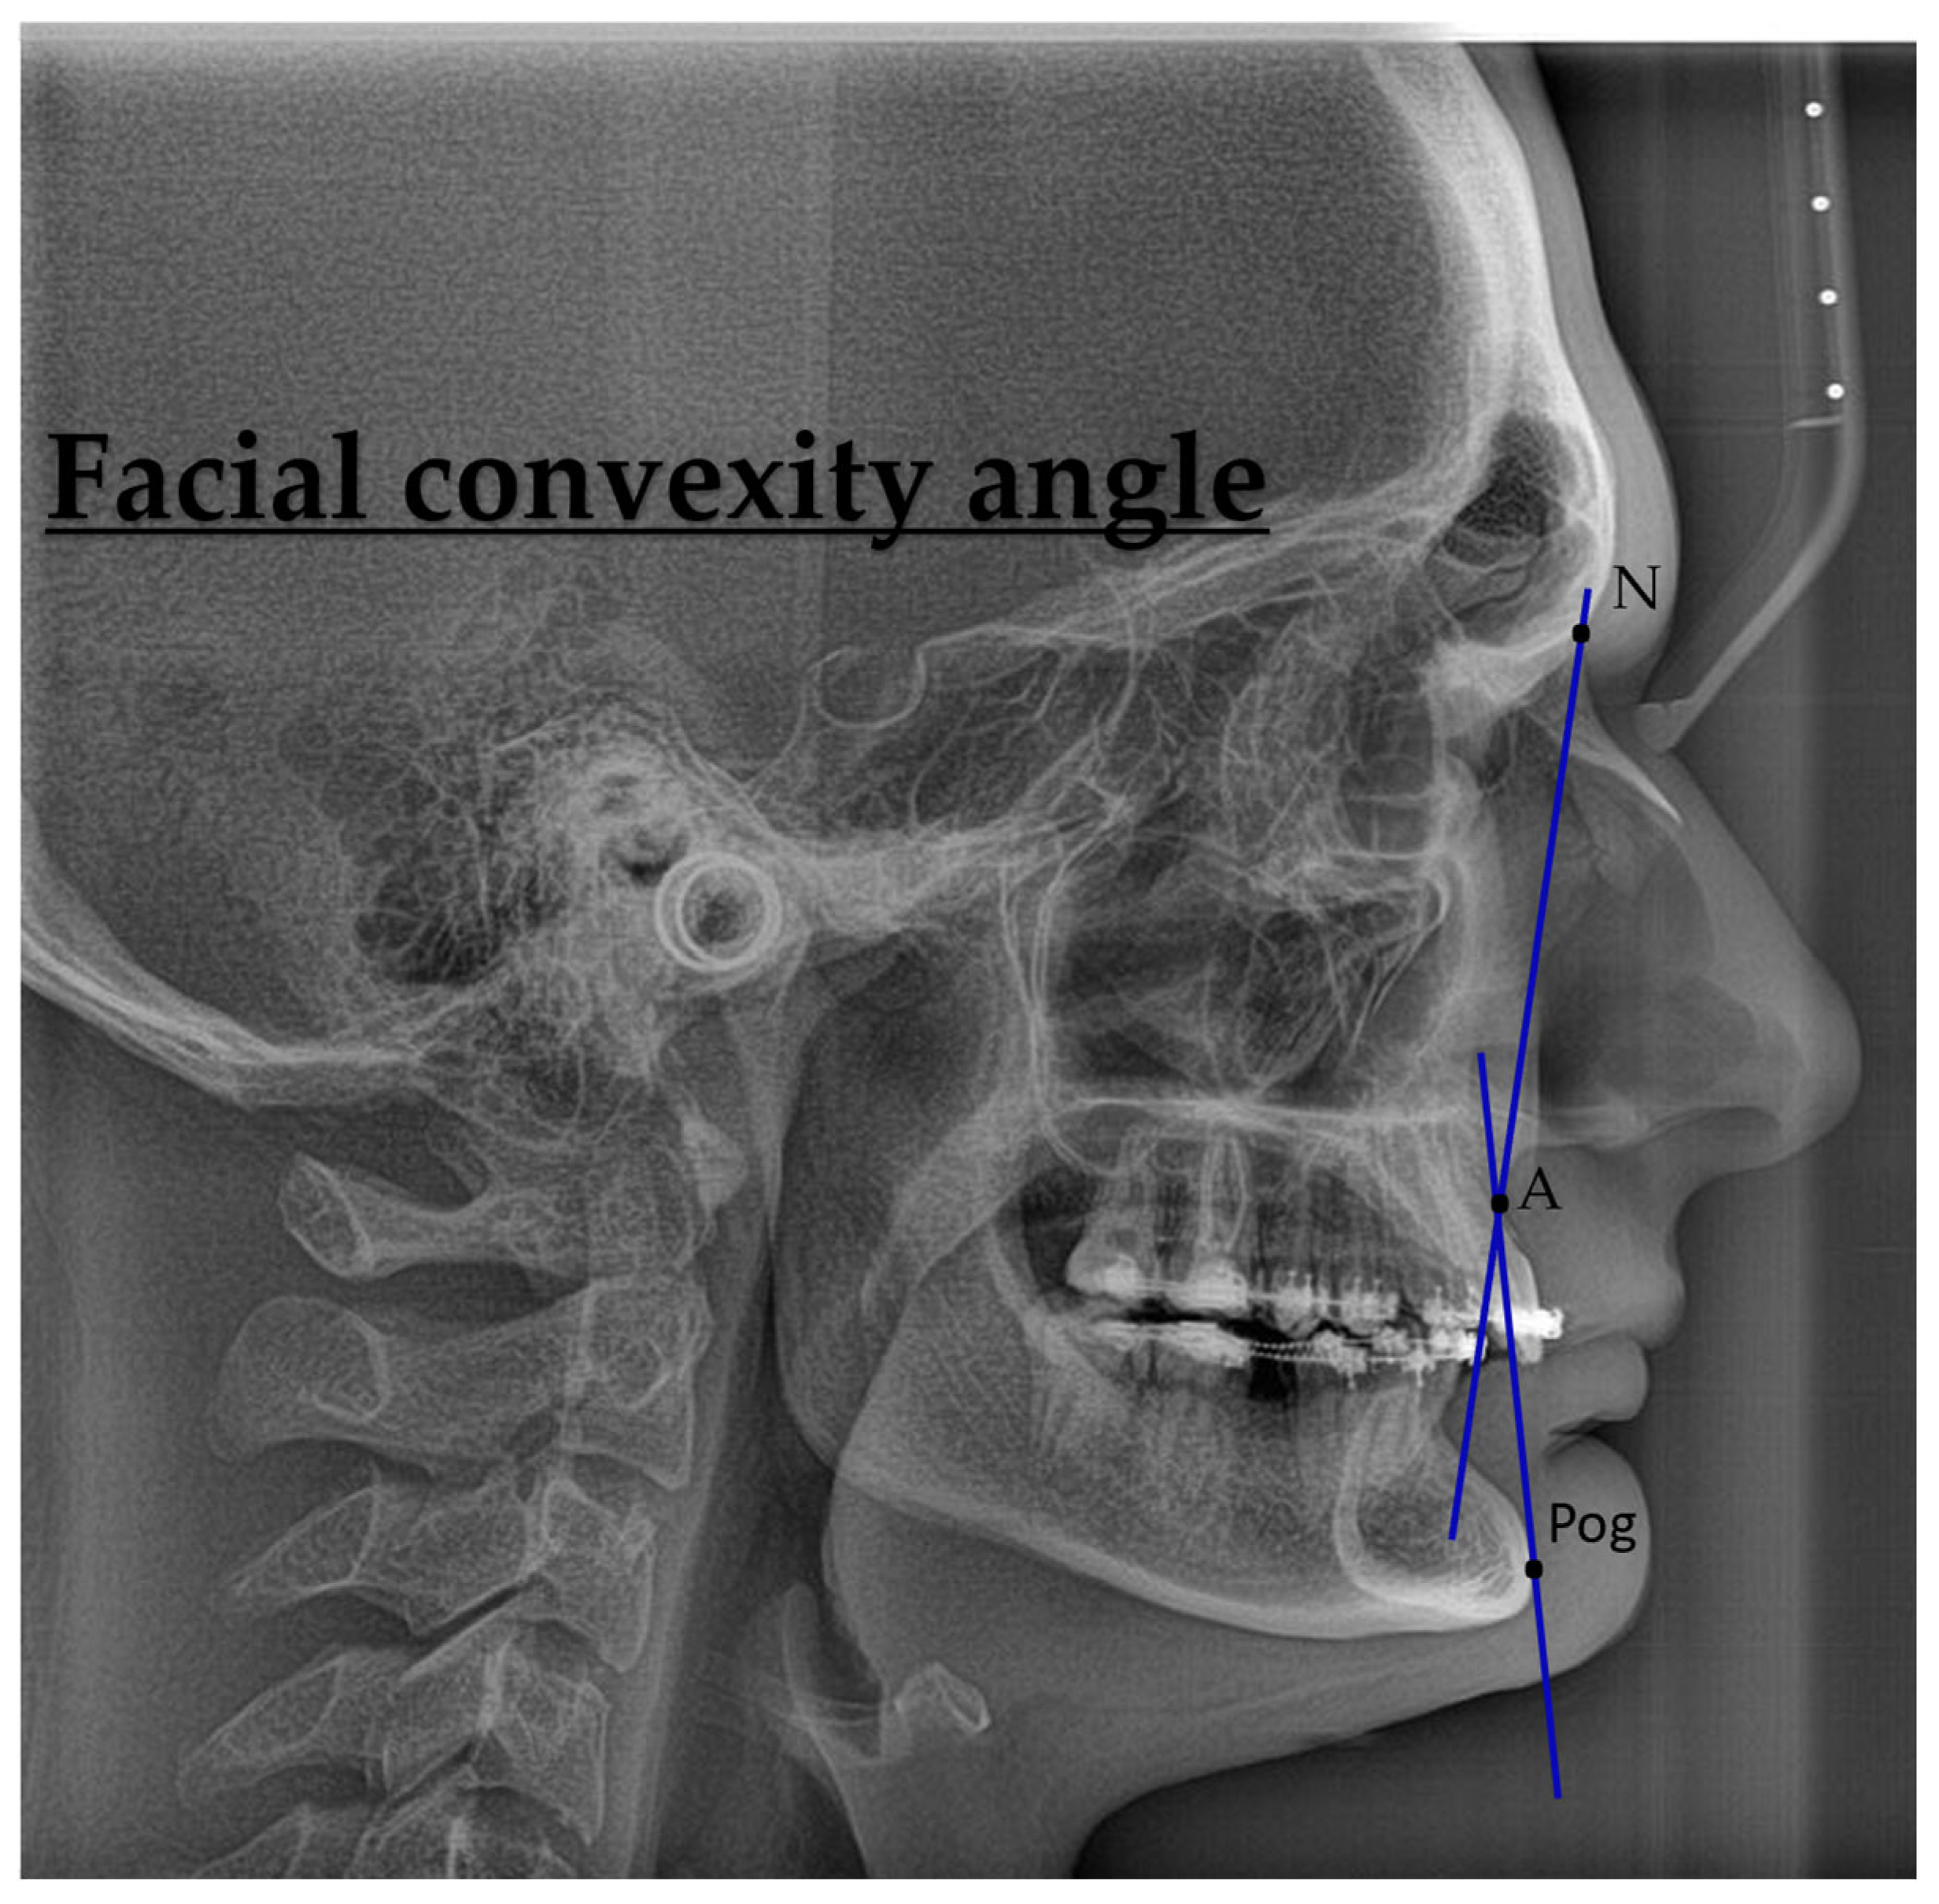

| Characteristic | Preoperative Median (IQR) | Postoperative Median (IQR) |

|---|---|---|

| Demographics | ||

| Age (years) | 28.0 (24.0, 33.0) | – |

| Sex, n (%) | Female: 11 (44%) Male: 14 (56%) | – |

| Skeletal parameters | ||

| SNA (°) | 83.6 (79.9, 84.9) | 86.3 (80.4, 89.0) |

| SNB (°) | 83.5 (76.8, 87.2) | 84.0 (81.0, 86.0) |

| ANB (°) | 0.9 (−4.9, 5.3) | 3.0 (−0.2, 4.5) |

| Pogonion to N-Perpendicular FH (mm) | 1.87 (−0.94, 2.31) | 1.4 (0.4, 2.6) |

| Dental parameters | ||

| U1–NA (°) | 26 (21, 28) | 22 (19, 29) |

| L1–NB (°) | 24 (17, 27) | 25 (19, 30) |

| Soft tissue parameters | ||

| Nasolabial angle (°) | 102 (92, 114) | 105 (91, 117) |

| Facial convexity (°) | 0 (−12, 7) | 2 (−6, 5) |

| Variable | Mean Difference | SE Difference | t | df | p-Value |

|---|---|---|---|---|---|

| SNA (°) | −3.123 | 1.24 | −2.511 | 24 | 0.019 |

| SNB (°) | −1.147 | 1.41 | −0.811 | 24 | 0.426 |

| ANB (°) | −1.980 | 1.00 | −1.977 | 24 | 0.060 |

| Pogonion to N-Perpendicular FH (mm) | −1.571 | 1.21 | −1.296 | 24 | 0.207 |

| U1–NA (°) | 0.465 | 1.87 | 0.249 | 24 | 0.806 |

| L1–NB (°) | −2.968 | 1.55 | −1.915 | 24 | 0.067 |

| Nasolabial angle (°) | −6.950 | 8.83 | −0.787 | 24 | 0.439 |

| Facial convexity (°) | −0.502 | 4.12 | −0.122 | 24 | 0.904 |